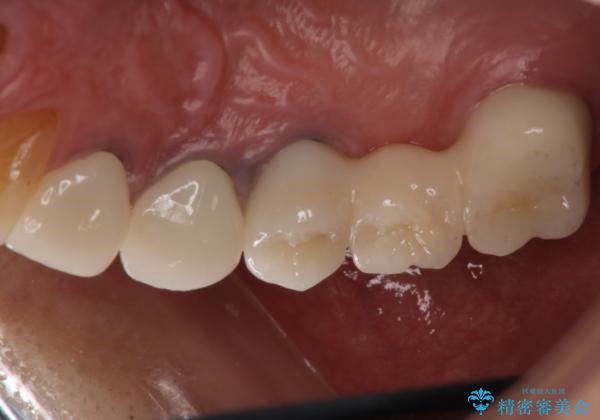

歯肉からの出血 適合の悪い銀歯をオールセラミックのブリッジにやり替え

以前の被せ物を除去し、仮歯に変えてすぐに異和感がとれました。

歯周治療を行い、歯肉が引き締まってから補綴治療しました。